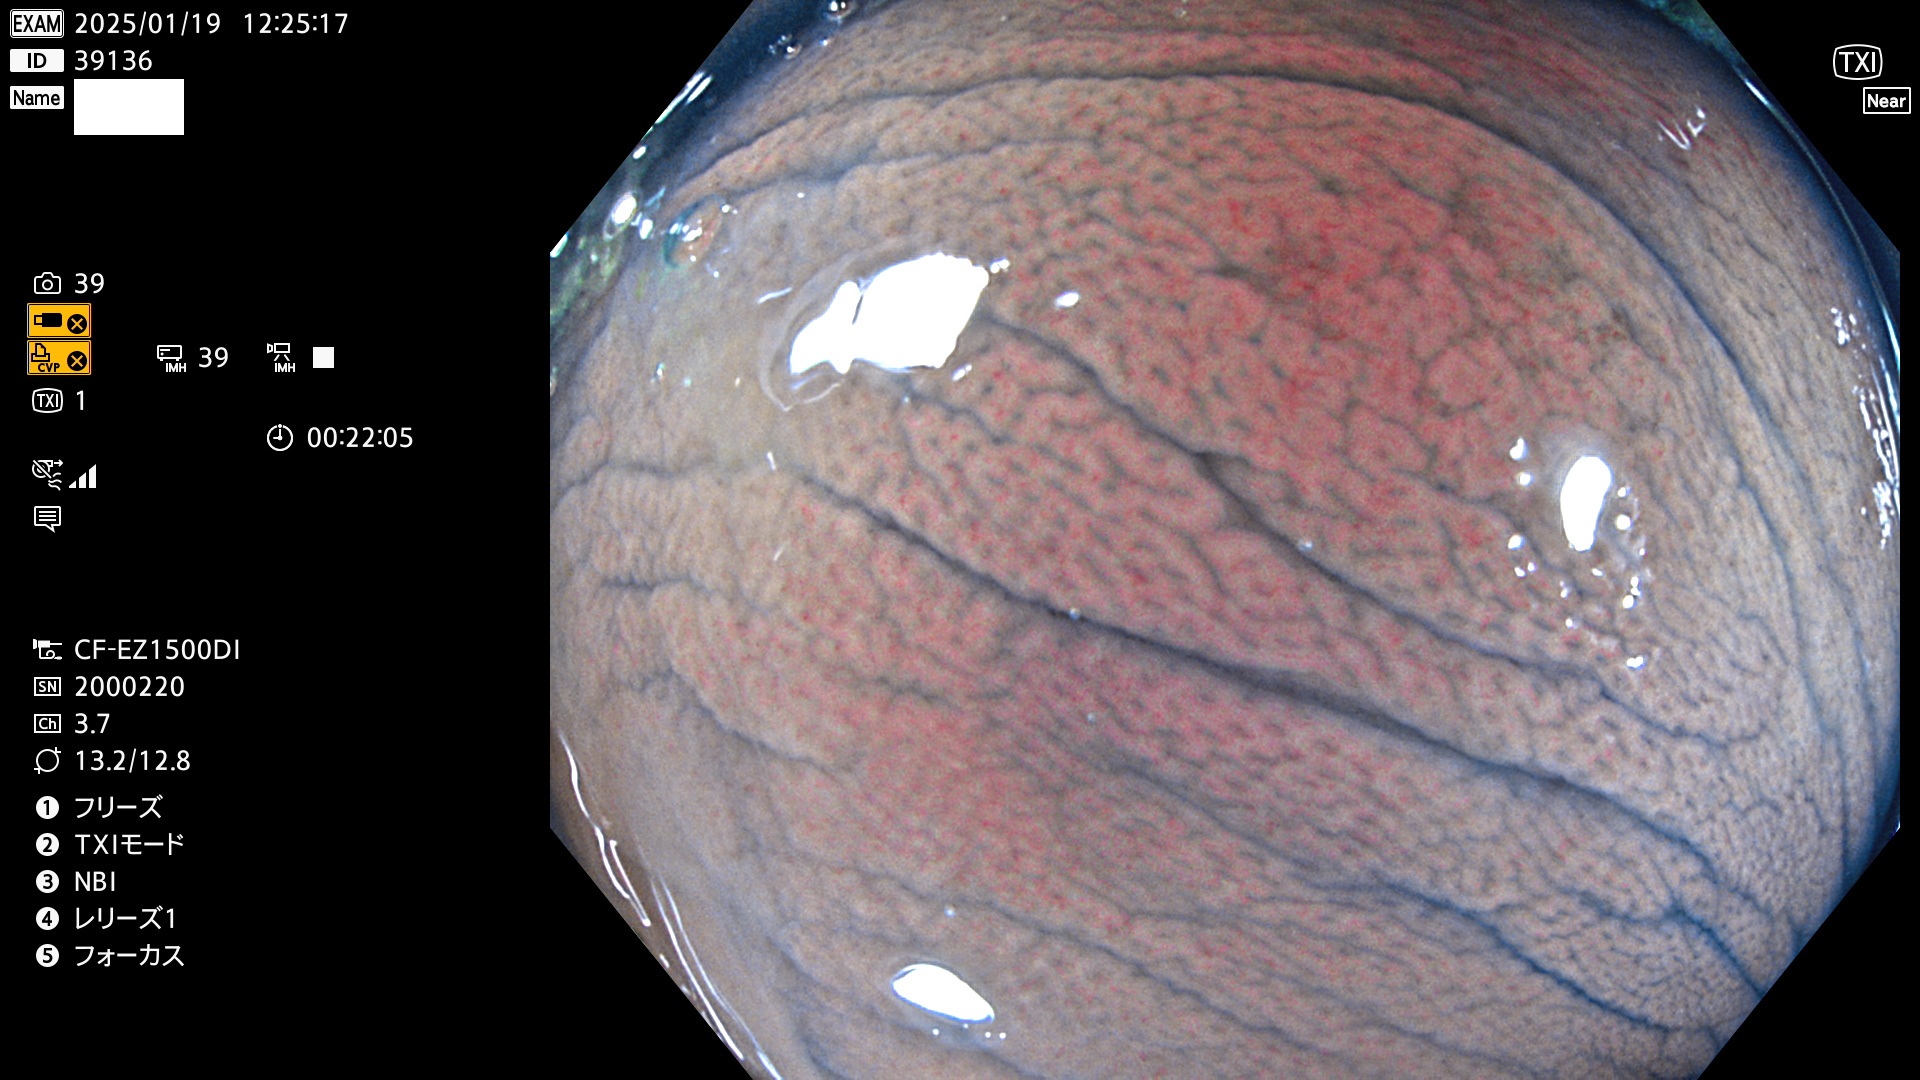

完全に平坦な物をUb、陥凹している物をUcと呼びます。最も発見が難しく危険な病変です。

毎週の検査(木・金・土・日)に発見されたUb、Uc型・腺腫を、その週の日曜の夜にUPし1週間、提示します。

抽出の対象期間 2025年1月16日〜1月19日の4日間(45件の検査)8個 (8/45=17%)